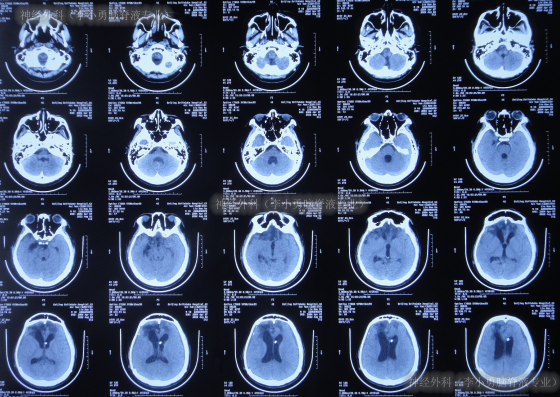

继续治疗1月期间出现数次呕吐,行胃肠镜检查未见异常(片子丢失),给予胃管及肠管置管,期间5次查头颅CT(图-5)均示脑室逐渐出现扩张,并加重。

图-5:5次查头颅CT

去骨瓣减压术后36天即2022年3月9日,复查头颅CT(图-6)示脑室扩张更严重了,脑膨出。

图-6:2022年3月9日头颅CT

去骨瓣减压术后43天即2022年3月16日,查头颅CT示仍严重脑积水(图-7)。

图-7:2022年3月16日头颅CT

因脑积水进一步加重,于2022年3月28日(去骨瓣减压术后55天),进行了脑室腹腔分流术。术后次日查头颅CT示脑室分流术后有出血(图-8)。

图-8:2022年3月29日头颅CT

脑室腹腔分流术后4天即2022年4月1日,查头颅CT示脑室明显缩小(图-9)。

图-9:2022年4月1日头颅CT

脑室腹腔分流术后8天即2022年4月5日,查头颅CT示脑室周仍有水肿(图-10)。

图-10:2022年4月5日头颅CT